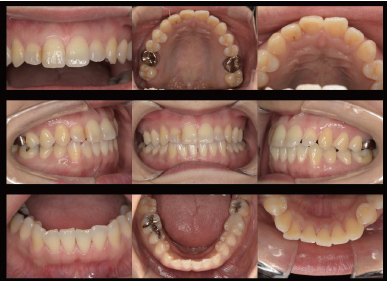

口腔内写真

すべての患者さんに初診や治療中のお口の中の

写真を撮影します。最初の状態や問題点または歯

ブラシによる歯肉の変化や治療の成果・経過を鏡

で見えない裏側まで患者さんご自身に見ていた

だくことができます。